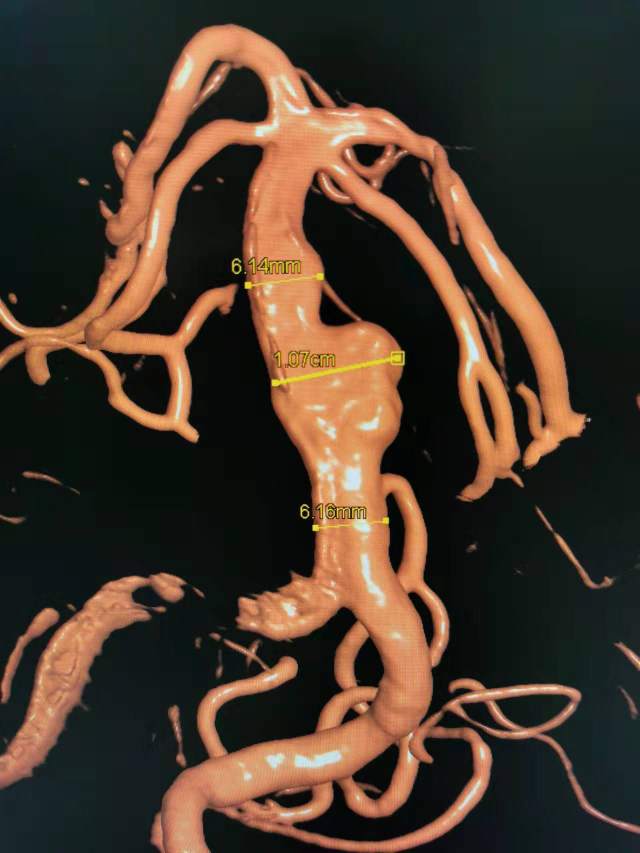

椎基底动脉冗长扩张症,是最棘手最复杂的脑血管病之一。患者从外地千里迢迢(3900余公里,仅高铁41小时)赶来东方医院诊治,期间症状不断加重(图2非真实大小)。术后一周复查:1、右侧肢体肌力明显改善;2、右侧肢体和枕部麻木症状明显改善;3、饮水呛咳缓解;4、共济失调明显改善;5、流涎消失;6、消失的味觉再次恢复。术后一周复查:血管修复良好(图5)。期待患者早日康复,早日奔赴工作岗位,保一方平安。